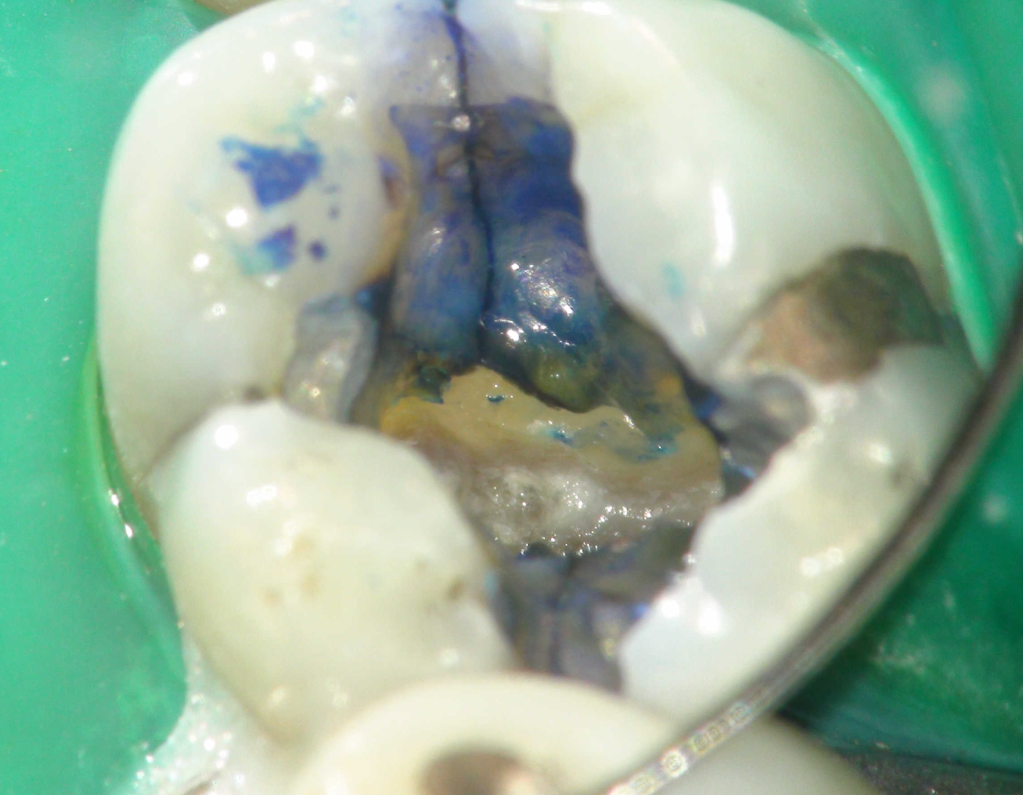

Fisura, remoción amalgama para explorar

Vertical root fracture